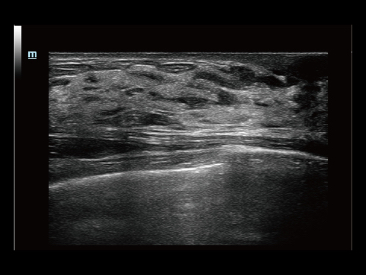

Sinds de oprichting van het bedrijf is Mindray voortdurend op zoek naar nieuwe manieren om het diagnostisch vertrouwen te vergroten. Resona 7 wordt aangestuurd door de meest revolutionaire ZONE Sonography?-technologie. Zijn nieuwe ZST+-tilt de kwaliteit van ultrasoundbeeldvorming naar een hoger niveau door middel van zoneacquisitie en kanaalgegevensverwerking.

Naast de hoogwaardige beeldvormingskwaliteit verbetert de Resona 7 tevens de klinische onderzoeksmogelijkheden met de revolutionaire V Flow voor vasculaire hemodynamische evaluatie, en de intelligentste vlakacquisitie van een 3D-gegevenssets voor de diagnose van het foetale, centrale zenuwstelsel. Met zijn combinatie van de meest intu?tieve, op vingerbewegingen gebaseerde multi-aanrakingsbediening en alle essenti?le klinische functies loopt de Resona 7 voorop in de nieuwe golven van ultrasoundinnovatie.